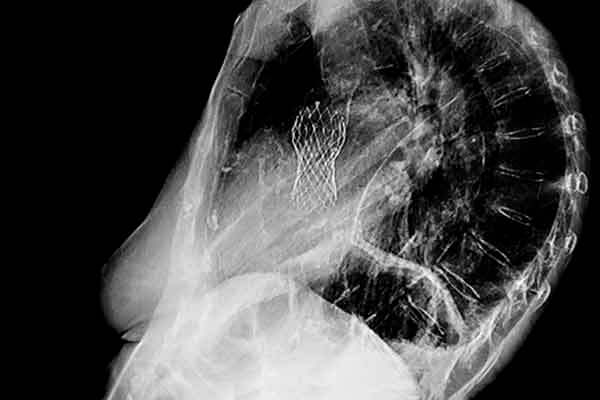

Use of Administrative Claims to Ascertain Outcomes in Randomized Clinical Trials for Transcatheter Aortic Valve Replacement: Findings From the Extending Trial-based Evaluations of Medical Therapies Using Novel Sources of Data (EXTEND) Study

Jordan B Strom | Richard A. and Susan F. Smith Center for Outcomes Research in Cardiology, Boston, MA

Results: Use of administrative claims to determine outcomes in randomized clinical trials showing promise.